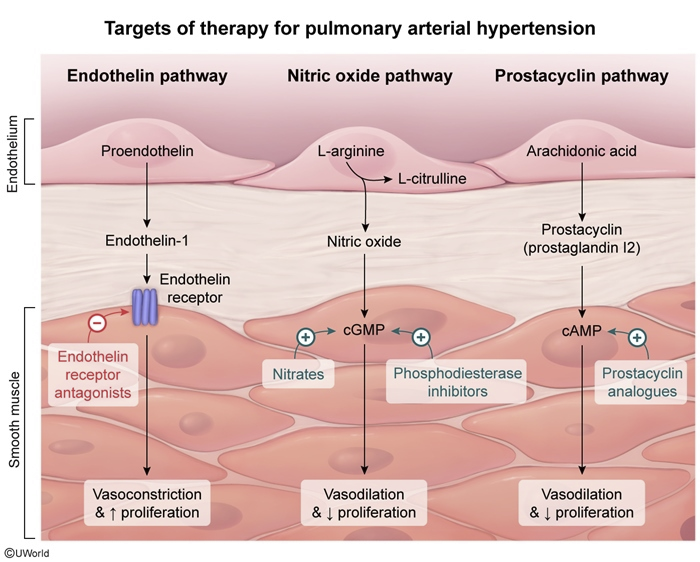

tx for persistent pulmonary htn of newborn (ie, in meconium aspiration syndrome)?

nitrous oxide

↑ cyclic GMP in smooth muscle cells of pulmonary arteries → dilation → ↓PVR, ↓ r→l shunting through ductus arterioisis

½ life of only few seconds = only vasodilates pulm